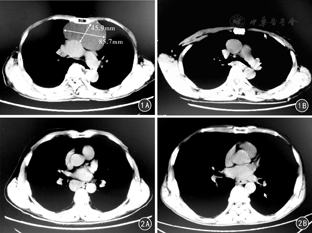

全组137例,全胸腔镜下手术110例(80.3%),辅助小切口25例(18.2%), 2例(1.5%)因术中损伤无名静脉中转开胸行血管修补。胸腔镜135例患者手术时间20~220 min,平均(105±48)min;术中出血量5~800 mL,平均(92±36)mL;术后胸引管引流1~9 d,平均(4.8±1.7)d;术后住院2~18 d,平均(5.2±1.8)d。典型病例见图1、图2。

术后并发症发生率5.8%(8/137),其中胸腔活动性出血行再次手术止血2例,术后肌无力危象3例,经机械通气、丙种球蛋白冲击等治疗后好转;经术后胸片检查发现膈肌麻痹2例,无明显症状;单侧肢体无汗1例,术后无改善。术后住院期间无一例死亡。术后病理诊断:胸腺疾病85例,其中胸腺瘤57例,胸腺增生17例,胸腺囊肿5例,胸腺癌6例;神经源性肿瘤28例,其中神经纤维瘤10例,神经鞘瘤12例,节细胞神经瘤6例;畸胎瘤10例;支气管囊肿4例;心包囊肿2例;淋巴管囊肿2例;脂肪瘤2例;霍奇金淋巴瘤2例;错构瘤1例;Castleman病1例。